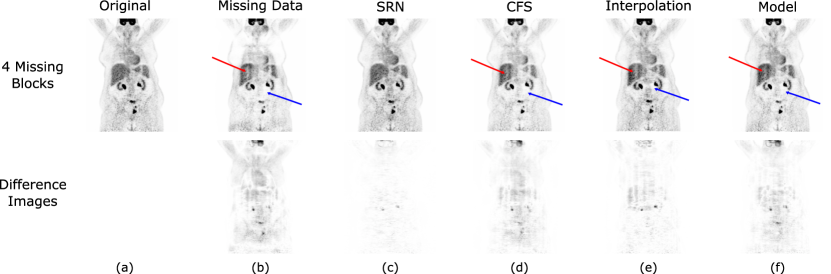

Coronal slices of reconstructed image volumes with four missing blocks from the test data set are presented in Figure 6 along with their difference image from ground truth. Visual inspection shows the Sinogram Repair Network reconstructed image is most similar to ground truth and has the least pronounced difference image. The images based on previous repair methods all show visual evidence of streaking as noted by the red arrow. They also contain areas of artificially low activity next to high activity as noted by the blue arrows. Both of these artifacts are confirmed by inspecting the difference image, but in contrast the Sinogram Repair Network image lacks these undesirable artifacts. The results from one and two missing blocks are not shown since differences in a single missing block are hard to distinguish visually and while images with two missing blocks do contain similar artifacts to the images shown, the visual differences are less pronounced.

Refer to caption

Figure 6: A reconstructed image space comparison of coronal slices from ground truth images and each of the repair methods with four simulated missing blocks. A visual inspection of the reconstructed and difference images show fewer artifacts with the Sinogram Repair Network. In comparison the other repair methods show evidence of streaks (red arrows) and low sensitivity (blue arrows).